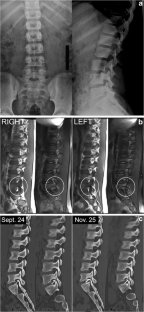

Atypical, unusual, and misleading imaging presentations of spondylolysis

Although lumbar spondylolysis is a widely known and easily recognizable condition in its typical presentation, there are some less well-known forms that may occasionally be challenging and/or demand special attention on imaging. Examples include: acute and/or incomplete lesions; unilateral defects; lesions at unusual levels (cervical, upper lumbar, and multi-level spondylolyses); iatrogenic lesions; non-isthmic spondylolysis; and spondylolysis related to underlying diseases. In addition to their atypical, uncommon or confusing imaging presentations, these forms of spondylolysis are far rarer than the classic type and have been described, to a great extent, in the surgical literature, thus reducing the awareness of radiologists about them and raising the potential for misdiagnosis and inadequate treatment. In this review the authors address these special manifestations of spondylolysis, stressing the more important features to be considered in the differential diagnosis and the impact of a precise diagnosis of spondylolysis on the patient’s care.